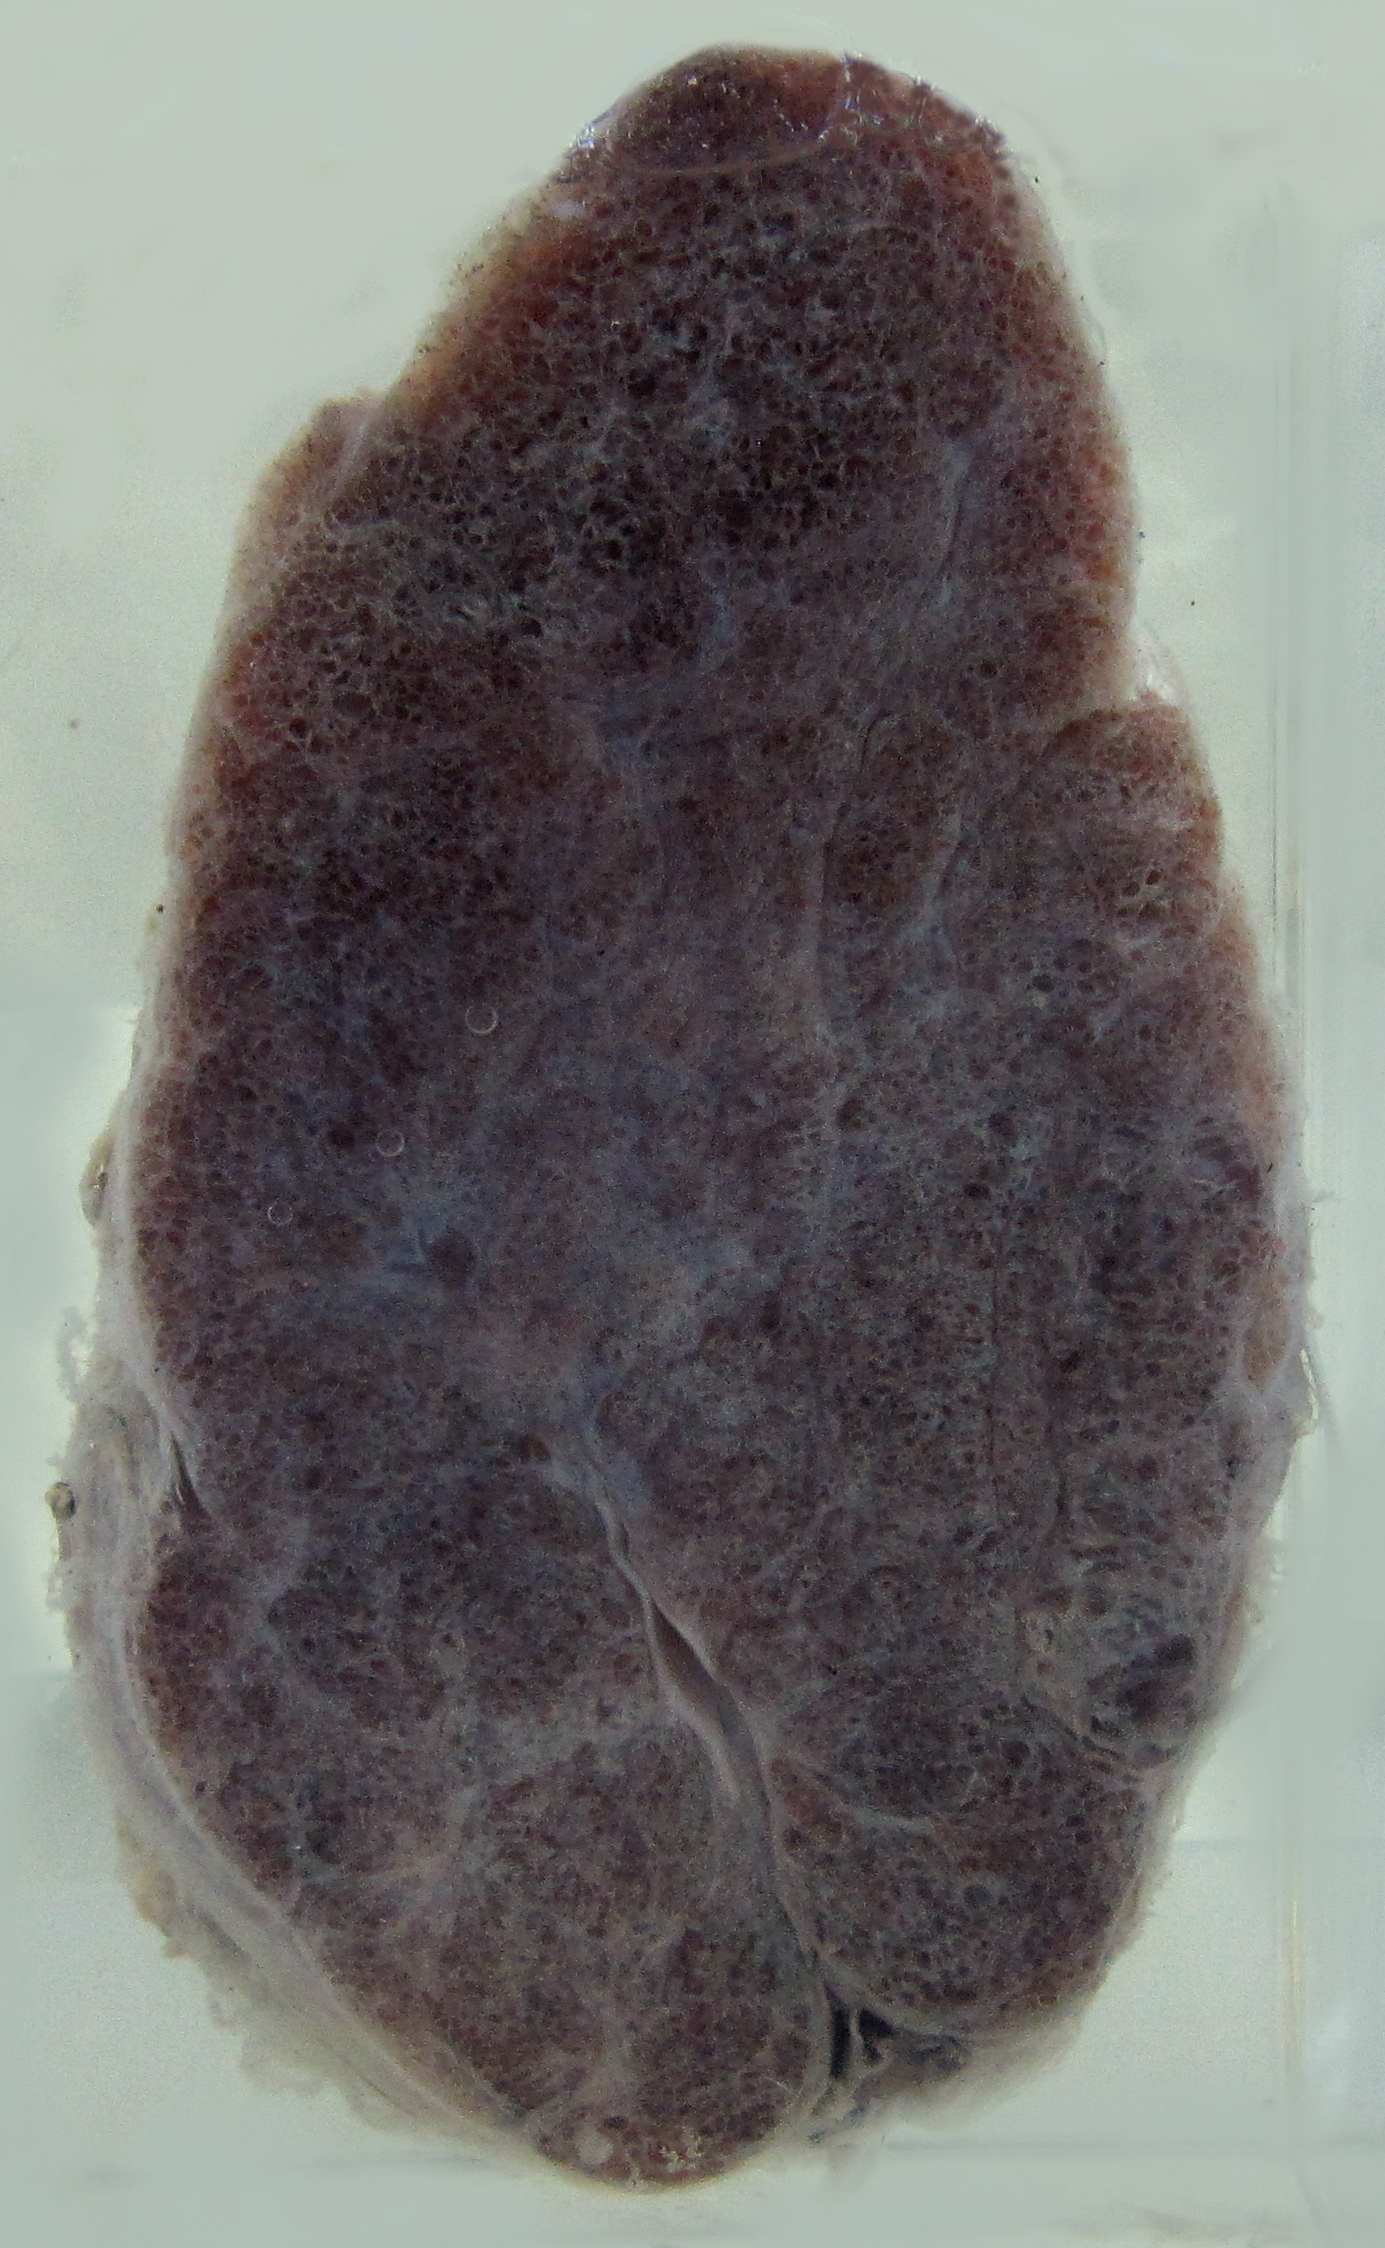

1. Diffuse colloid goite